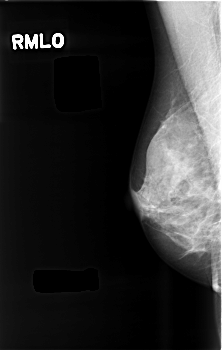

C_0482_1.RIGHT_MLO

RIGHT_CC LINES 4552 PIXELS_PER_LINE 2912 BITS_PER_PIXEL 12 RESOLUTION 50 NON_OVERLAY

RIGHT_MLO LINES 4544 PIXELS_PER_LINE 2880 BITS_PER_PIXEL 12 RESOLUTION 50 NON_OVERLAY